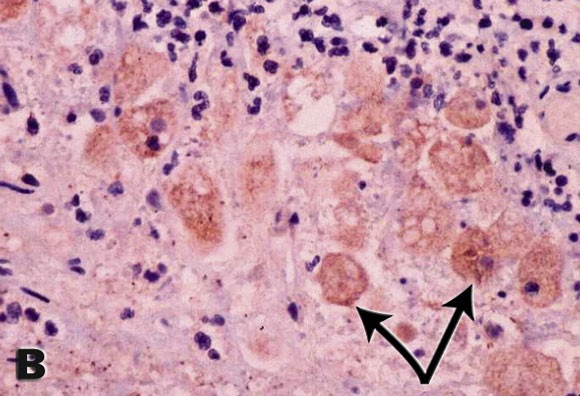

Histological sections of the surgical specimen showed changes typical of acute suppurative appendicitis. Closer examination, however, revealed numerous round-to-oval structures resembling trophozoites (see Box). When the possibility of invasive amoebiasis was raised, staining of the section with Entamoeba histolytica-specific sera confirmed the diagnosis. E. histolytica serology was negative.

The diagnostic method of choice for amoebic colitis is testing for parasite antigen in stools.1 In this case, for the first time, the species-specific antibody normally used in the stool antigen test was adapted for immunohistochemistry and confirmed E. histolytica infection. Possible alternative methods for confirming the diagnosis include the polymerase chain reaction (PCR) or detection of E. histolytica-specific antibodies or parasite antigen in patient serum.1 However, PCR is not readily available outside research laboratories. The sensitivity of the E. histolytica antibody test in intestinal disease is 52%, a likely explanation for the negative serological test.